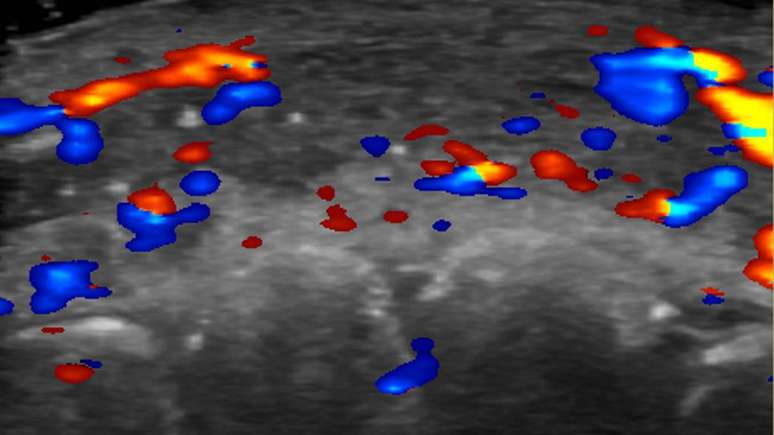

Um ultrassom dos lábios de um paciente mostra a ausência de fluxo sanguíneo

Foto: Rosa Sigrist e RSNA / BBC News Brasil

Em quase metade dos casos avaliados, ultrassonografias mostraram ausência de fluxo sanguíneo em vasos pequenos que conectam artérias superficiais àquelas mais profundas do rosto.

E em um terço dos pacientes, fluxo sanguíneo estava ausente nos principais vasos sanguíneos.